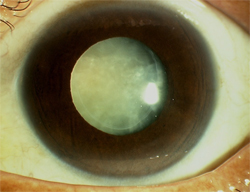

白内障

作为全球第一大致盲眼病,可能大家都觉得白内障一向是属于年长人士的疾病,但近年白内障有年轻化的现象,原因之一就是高度近视。

白内障是眼球内晶状体全部或部分混浊,高度近视容易并发该病,且手术效果也比没有高度近视病史的人群差。

白内障会出现视力减退和视物模糊,严重时会出现视物模糊、畏光、看物体颜色较暗或呈黄色等情况。